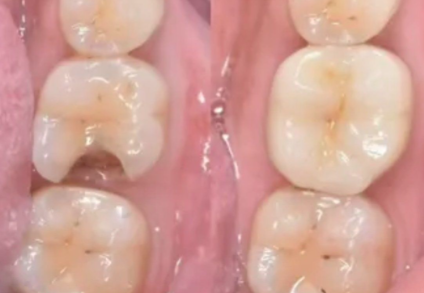

1. 种植牙:可开展韩国登腾、瑞典诺贝尔等多种种植体系,还能进行高难度的ALL - ON - 4种植牙和穿翼种植牙。专门设置种植室、无菌层流手术室和消毒供应室,降低感染风险。